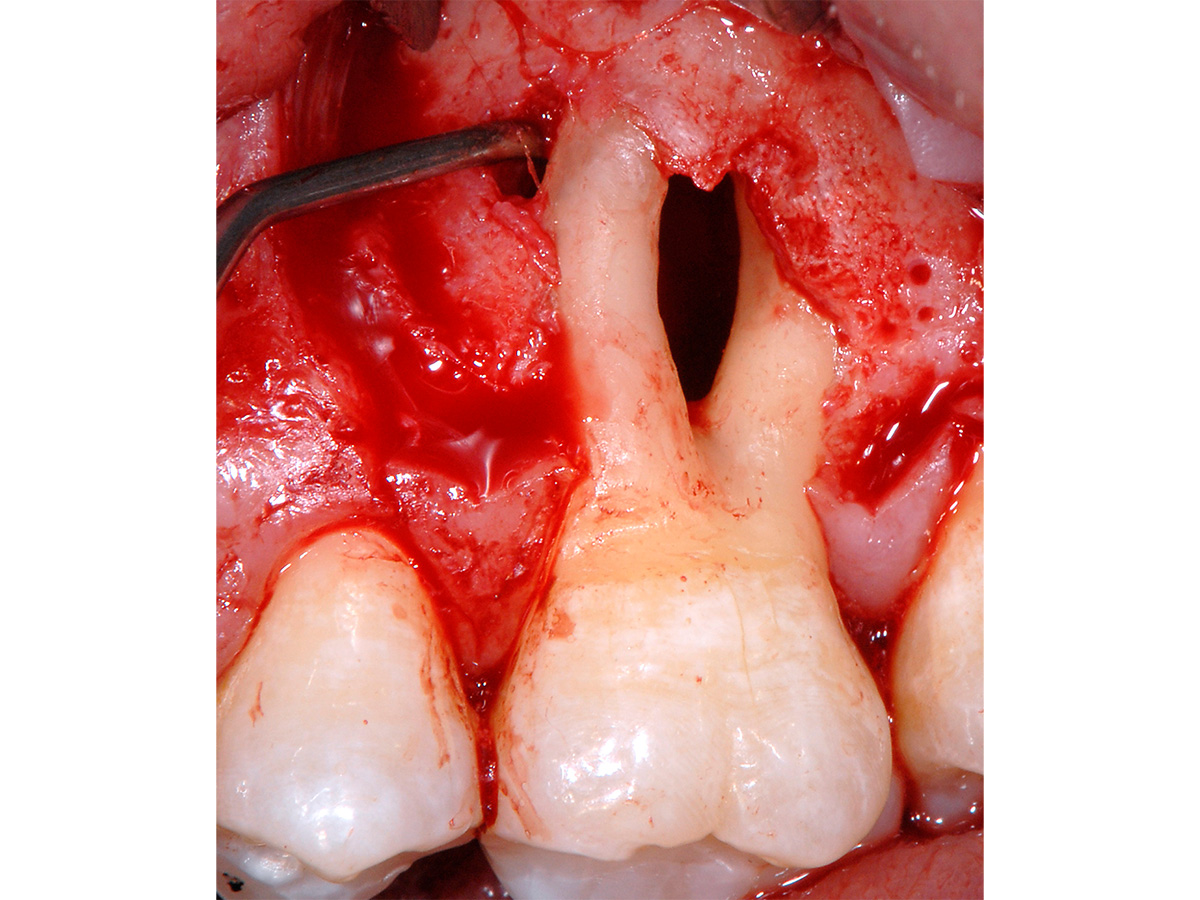

Abbildung 1

Klinische Ausgangssituation: Ausgedehnter parodontaler Furkationsdefekt an Zahn 26 in Kombination mit marginaler Gingivarezession.